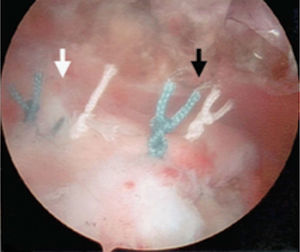

En la técnica de fila sencilla o una sola fila se colocan anclajes de 5,0 o 5,5 mm (titanio biodegradable o peek) en el margen lateral de la tuberosidad mayor, se pasan los puntos a través del tendón aproximadamente a 15 mm en sentido medial al borde de la rotura. Se utiliza el número de anclajes de acuerdo con el tamaño de la rotura. También se debe tener en cuenta con cuántas suturas está cargado el anclaje. En la mayoría de diseños tiene dos suturas reforzadas. Para las roturas en forma creciente se puede realizar la reparación con puntos sencillos, pero, cuando son lesiones de mayor extensión o en forma en L, se recomienda combinar puntos de borde a borde y fijación con anclajes (figs. 14–16).

En la técnica de doble fila se colocan uno o dos anclajes mediales en el borde articular de la cabeza humeral, se pasan puntos sencillos a través del tendón y se anudan las dos suturas de cada anclaje con nudos deslizantes bloqueados. Los anclajes laterales se colocan en el borde lateral de la tuberosidad mayor y se anudan con las suturas mediales, ya sea con nudos deslizantes bloqueados o con los sistemas de no nudos existentes en el mercado. Una de las principales complicaciones en la reparación del manguito de los rotadores es la rerrotura, pero es muy importante tener en cuenta que en muchas ocasiones no existe una correlación directa entre una rerrotura, ya sea parcial o completa, con los resultados clínicos y funcionales44. Sin embargo, existe una relación directa entre la cicatrización y la fuerza postoperatoria (figs. 17–19).